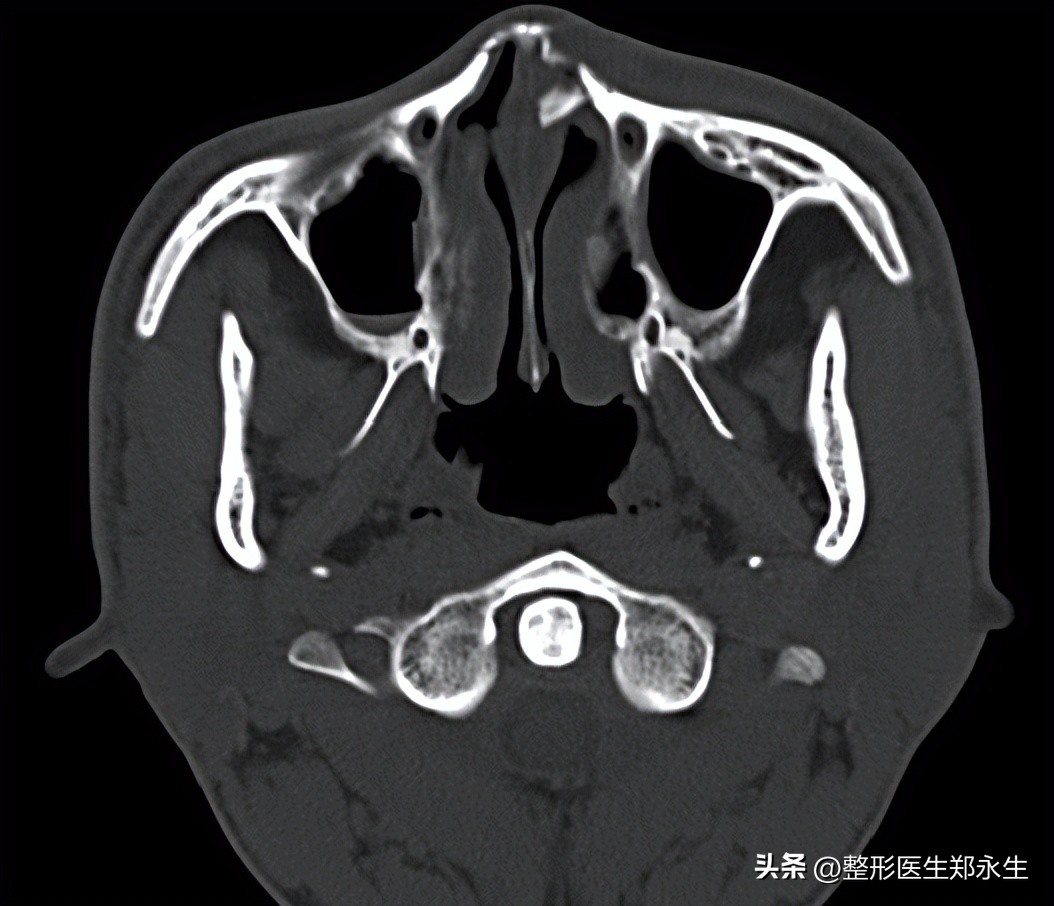

以上只是根据临床、学术研究分析得出的大概情况,而现实歪鼻情况更为复杂,医生需要CT片子才能做出最准确的判断。当然从外观来判断也有一定的参考价值,歪鼻的朋友不妨对照镜子看看你属于哪一种情况,留在评论区,有时间帮大家看看给出我的改善意见,让大家少走弯路。